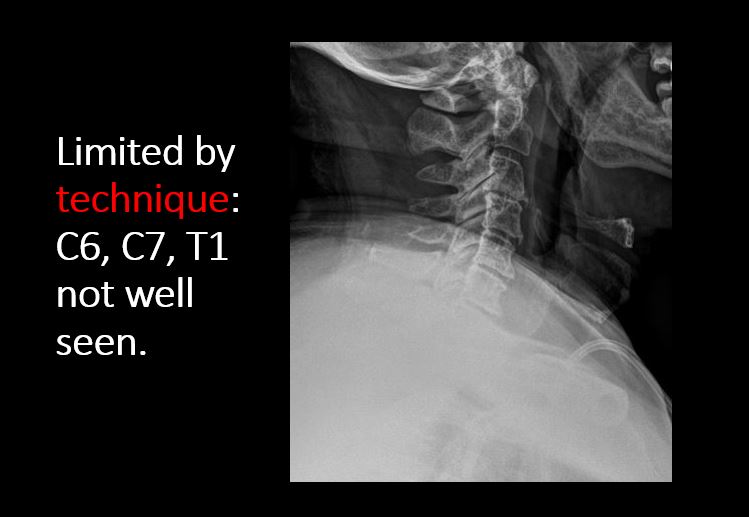

Section 1 Submit Findings C442 Findings Technique The craniocervical junction and/or C7-T1 are not entirely included on the exam. Yes No The exam is over or under penetrated. Yes No The exam is limited by overlying structures, bones or soft tissues, body habitus, patient positioning, support devices, or motion. Yes No Prevertebral and paravertebral soft tissues The soft tissues anterior to C1-C7 are widened or the prevertebral fat stripe is not seen. Yes No The paravertebral soft tissues are abnormally widened. Yes No N/A There is calcification, foreign body, abnormal air, or other abnormal density in the prevertebral or paravertebral soft tissues. Yes No Spinal alignment The distance between the basion and the posterior axial line is > 12 mm. Yes No The distance between the basion and the tip of the dens is > 12 mm. Yes No The atlanto-axial joint distance is > 2 mm on the lateral view. Yes No The distance between the dens and the lateral masses of C1 is abnormally asymmetrically widened on an odontoid or AP view. Yes No N/A The lateral mass(es) of C1 abnormally override(s) the articular pillar(s) of C2 on an odontoid or AP view. Yes No N/A The anterior vertebral body line, posterior vertebral body line, articular pillar line, and/or spinolaminar line is/are abnormal. Yes No The articular pillars or lateral masses, lamina, or other posterior elements are rotated or displaced into the spinal canal or the interlaminar clear zone of the spinal canal. Yes No The visualized spinous processes are malaligned on the AP view or distracted on the lateral view. Yes No There is reversal or straightening of the normal lordosis or abnormal angulation/curvature or motion of the cervical spine on frontal, lateral, flexion and/or extension views. Yes No Vertebral bodies, posterior elements, and base of skull There is a fracture or deformity of the base of the skull or occipital condyles. Yes No There is a fracture or deformity of the anterior or posterior arch of C1. Yes No There is a fracture or deformity of the lateral mass(es) of C1. Yes No There is a fracture or deformity of the dens or C2 vertebral body. Yes No There is a fracture or deformity of the pars interarticularis/articular pillars or other posterior elements of C2. Yes No There is a fracture or distraction of a C3-T1 vertebral body, transverse or spinous process, or other posterior element. Yes No There is evidence of an end plate avulsion or other fracture. Yes No There is displacement of a fracture fragment into the soft tissues, spinal canal, or interlaminar clear zone of the spinal canal. Yes No There is anterior wedging or compression of a vertebral body or end plate. Yes No There is evidence of an aggressive disease process manifest as a lytic, sclerotic, or destructive abnormality of a vertebral body, end plate, pedicle, lamina, articular pillar, transverse or spinous process. Yes No There is focal or diffuse abnormal mineralization. Yes No Disc spaces and facet joints There is distraction or focal widening of a disc space. Yes No There is anterolisthesis, retrolisthesis, subluxation, or rotational abnormality of a disc space. Yes No There is widening, rotational abnormality, or displacement of facets at any motion segment (e.g. locked or jumped, perched facets, or fracture dislocation). Yes No There is disc space narrowing with or without erosive or sclerotic changes of the end plates other than from degenerative change. Yes No There is facet joint narrowing or sclerosis other than from degenerative change. Yes No Additional soft tissues and bones (neck, airway, upper thorax, ribs) The included maxillofacial region, thoracic spine, ribs, or other bones of the upper thorax are abnormal. Yes No There is air or a foreign body or other abnormality in the soft tissues of the lower head, neck or upper thorax. Yes No There is an apical mass, thickening, pleural cap or effusion, or pneumothorax. Yes No N/A The airway is narrowed or displaced. Yes No There are post surgical changes of the bones or soft tissues of the lower head, neck, or upper thorax. Yes No There is an abnormality or complication of post-surgical hardware. Yes No N/A There are support lines or tubes in an abnormal position. Yes No Other findings There are degenerative changes or other existing conditions that might be contributing to symptoms which can or should be further evaluated non-emergently. Yes No